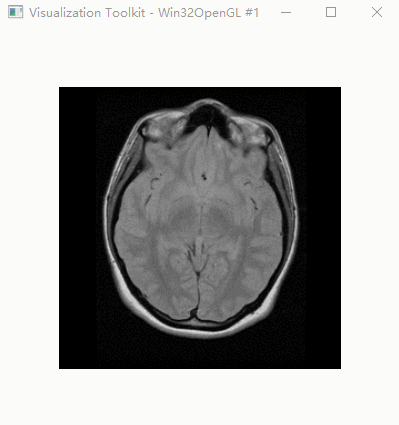

效果

脑部CT图像